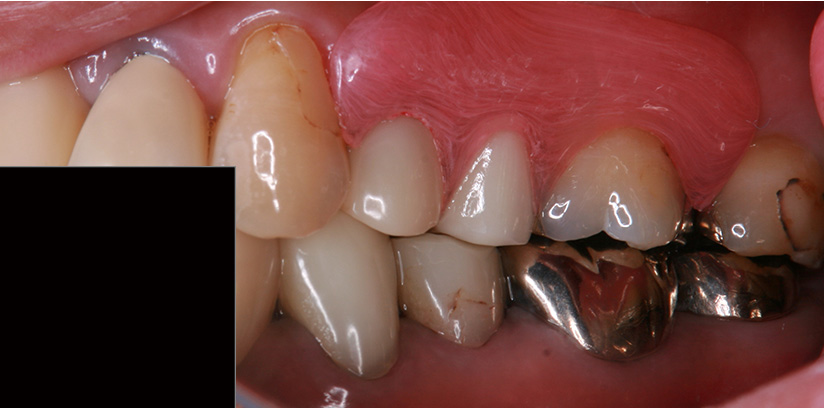

症例紹介

1歯義歯治療の例

術前・術後の比較

| 患者属性 | 50代 女性 |

|---|---|

| 主訴 | 左上の歯ぐきが痛む |

| 診断 | 左上5 歯根破折 |

| 補綴装置 | ノンクラスプデンチャー |

| 治療期間 | 約2ヵ月 |

| 通院回数 | 2回 |

| 治療費 | ノンクラスプデンチャー治療(1歯):110,000円(税込) |

| 治療内容 | 左上5の抜歯術を行い、治癒期間(約1か月)を得て、2回の義歯治療で義歯を作成しています。 |

| リスクと副作用 | 歯がないところの横の歯(隣在歯)に義歯をひっかけるため、その支えとなる歯には、ブリッジ治療と同様の影響があります。 |